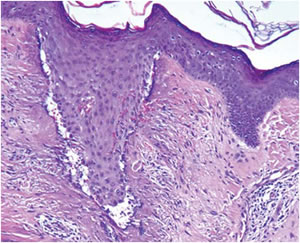

Histology

| Immediate post-treatment histology | Day four histology |